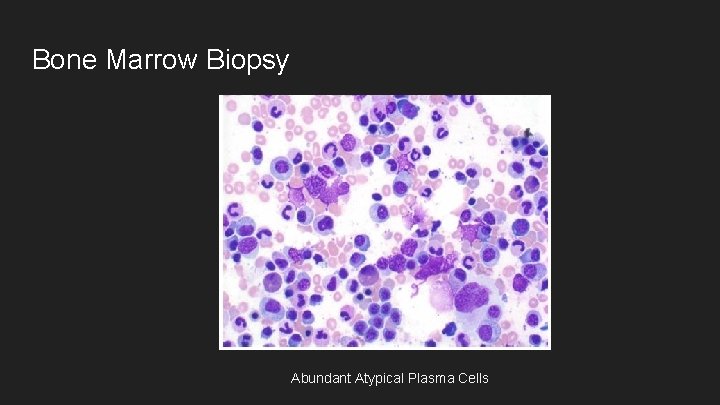

Bone Marrow Biopsy Abundant Atypical Plasma Cells